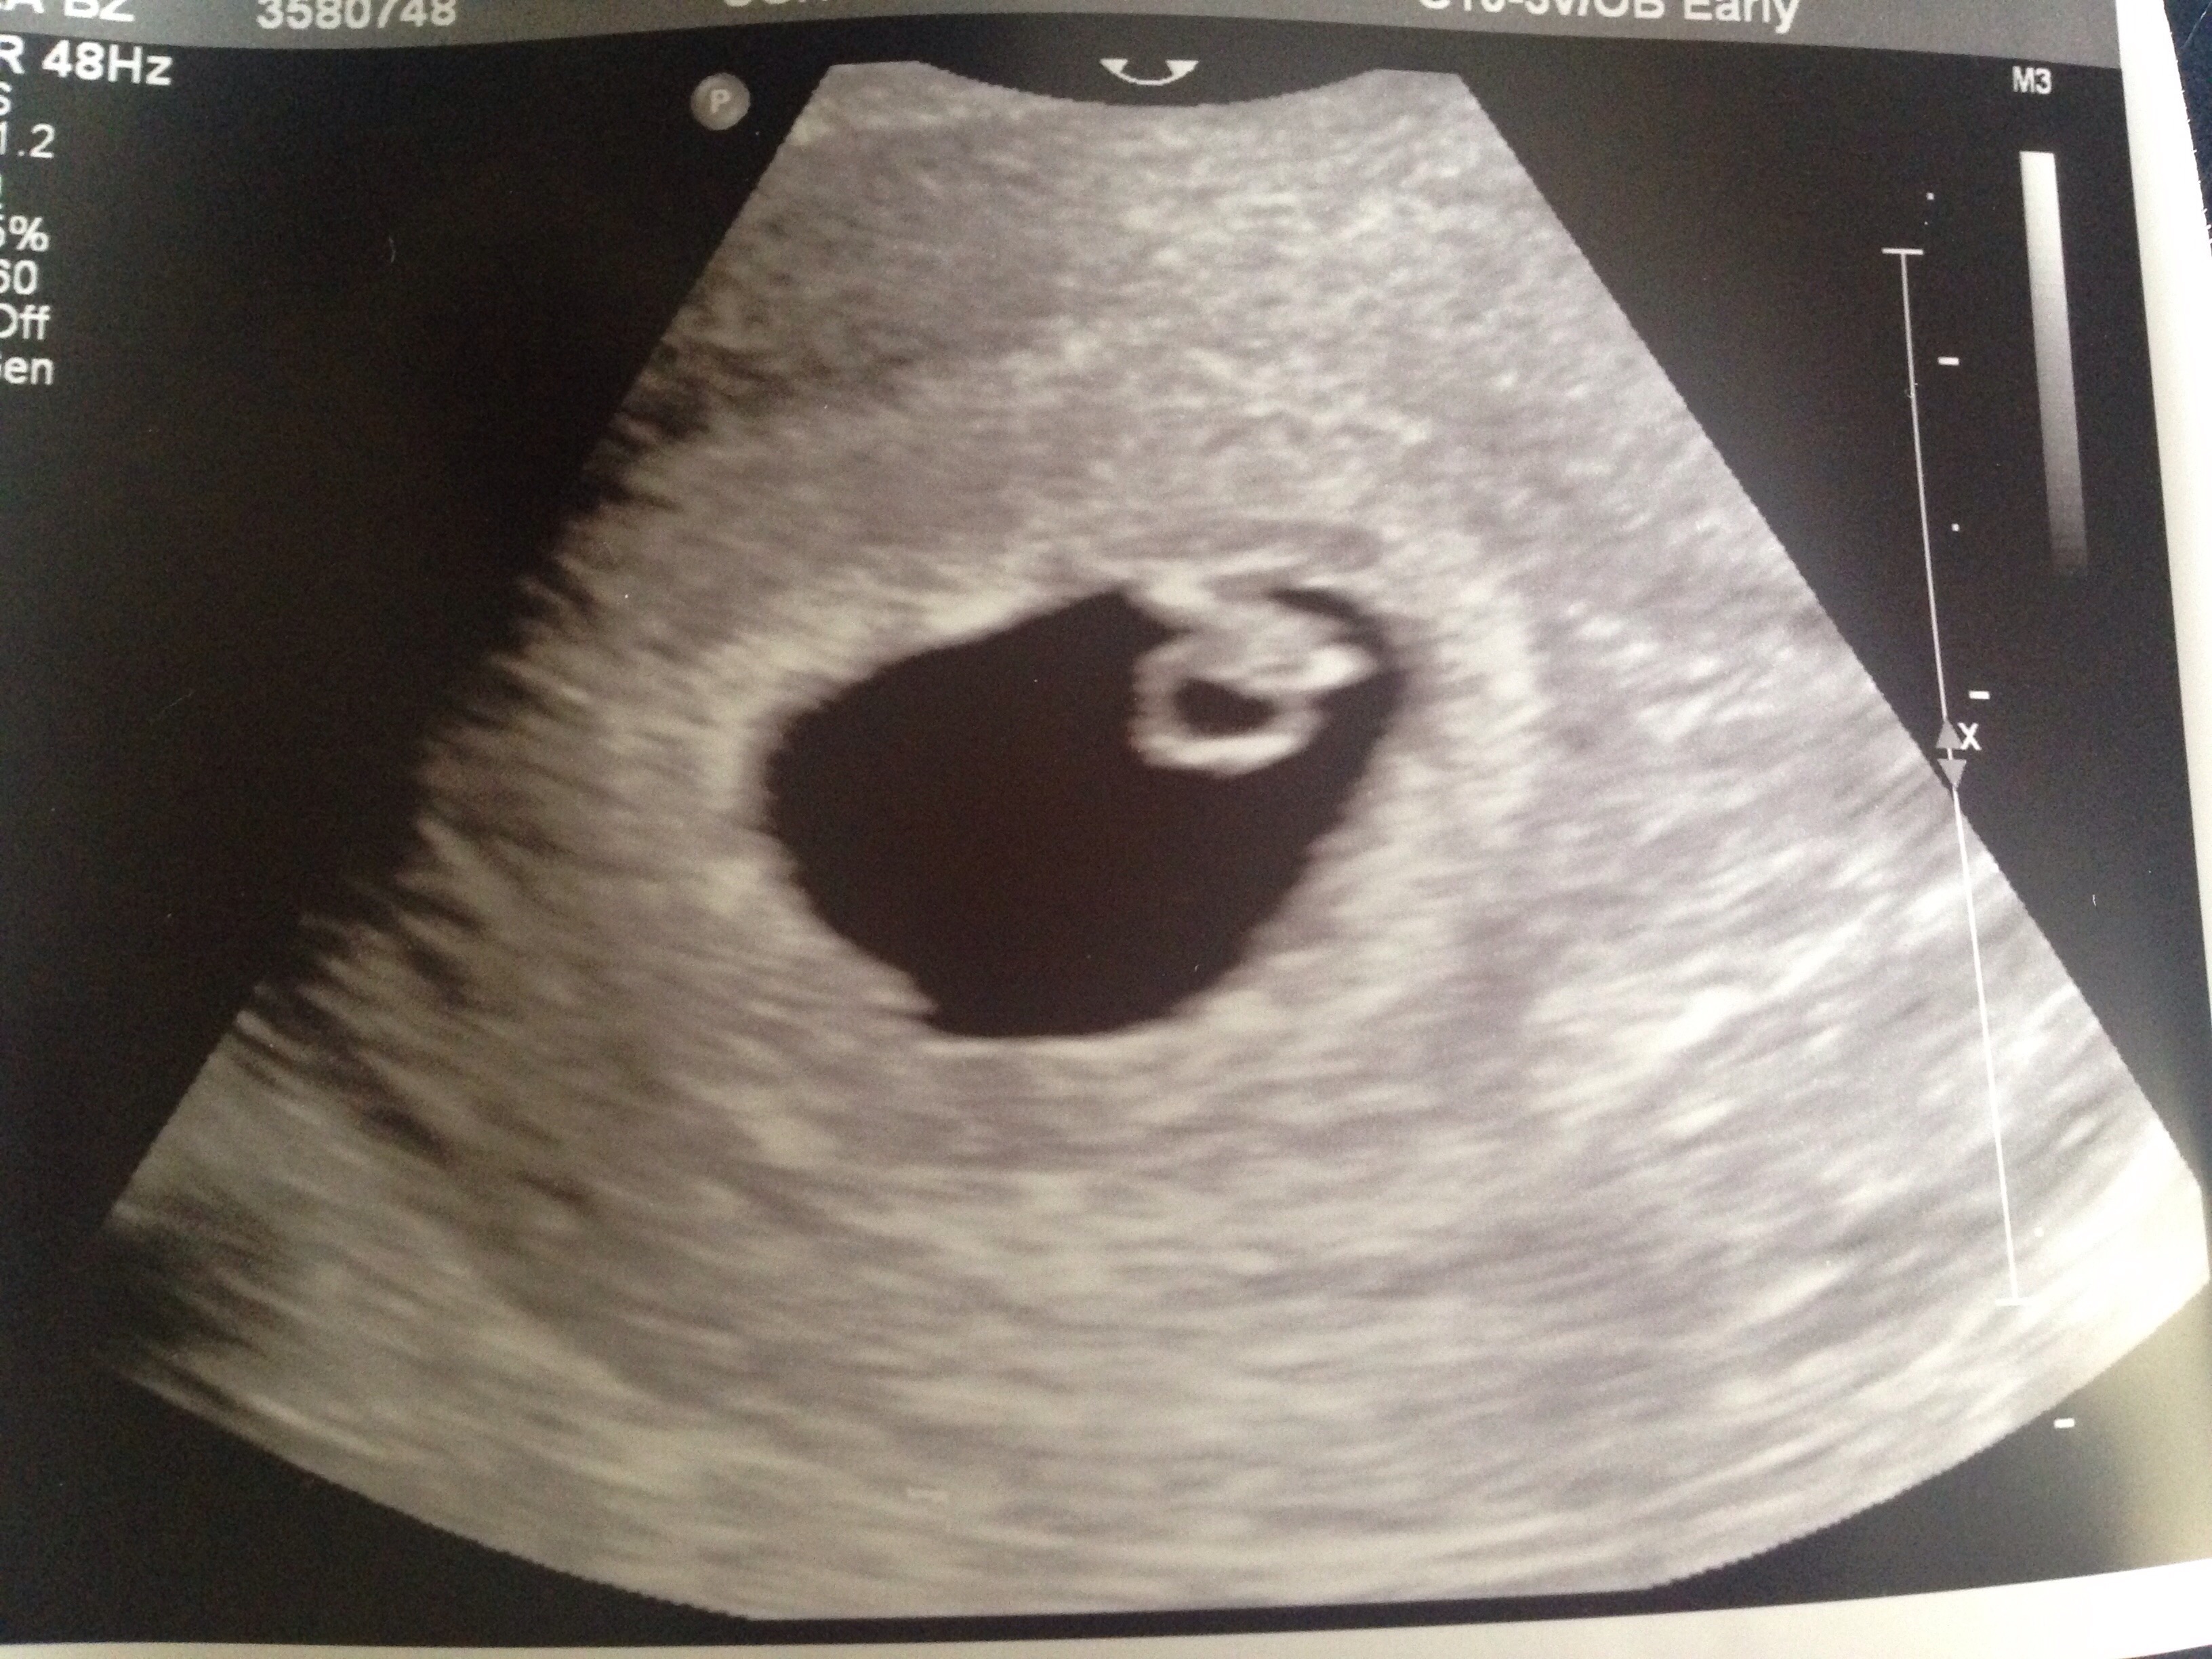

Had my first ultrasound today...5w3d and sure enough there is a sack and yolk sack....super excited!!!! Ill have another done in a couple weeks to look for a heartbeat!